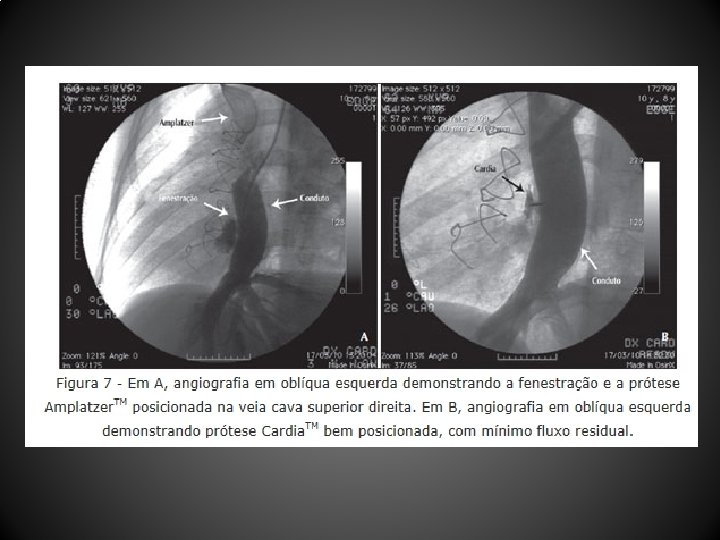

Resultados • Entre abril de 2004 e dezembro de 2010, 12 pacientes (média de idade, 103, 1 + 88, 6 meses; peso, 29, 9 + 12, 7 kg) submetidos a CF (10 tubos extracardíacos, 2 túneis intra-atriais) foram tratados 44, 1 + 26, 7 meses após a CF • Um paciente não tolerou o teste de oclusão com o balão, sendo contraindicado o procedimento • As próteses utilizadas foram: Helex. TM (4 pacientes), Amplatzer. TM (2 pacientes), Cardia Atriasept. TM (2 pacientes), Figulla. TM (1 paciente), Cera. TM (1 paciente), e 1 stent coberto Cheatham-Platinum. TM • Após a oclusão da fenestração, a saturação de oxigênio aumentou significativamente (82, 1 + 6, 5% para 95, 2 + 3, 2%), sem aumento significativo da pressão venosa central (12, 4 + 2, 6 mm. Hg para 14, 5 + 2, 3 mm. Hg) nem queda do débito cardíaco • Após o procedimento foi observado shunt residual imediato em 5 pacientes, que desapareceu antes da alta